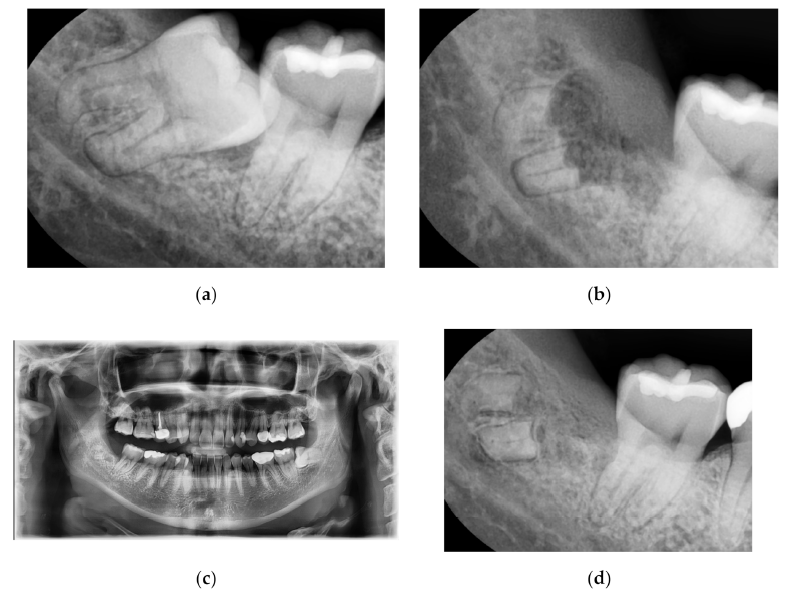

전신질환이 없는 30세 남성 환자

7년 전 이상 위치 때문에

오른쪽 하악 사랑니가 발거됨.

부분적으로 뽑힌 사랑니 주변 잇몸에

염증이 재발하는 것 외에

인접한 두 번째 어금니에 대한 통증과

과민반응을 유발(그림 a).

김영삼 원장님은 수술 전 엑스레이에서

뿌리 끝 부분에 해당하는 어두운 부위를 보고

뿌리와 피질뼈의 설측 부분 사이에

엄격한 접촉이 있음을 발견.

안전한 수술을 하기 위해

수술 전에 CBCT를 시행.

합병증을 유발할 수 있는 완전 발거 대신

치관절제술만 하기로 결정.

의도하지 않은 치관절제술의 예로서

그림 b는 10일 후, 봉합 실을 제거하는 동안

어떻게 뼈가 아물고

남아 있는 뿌리 부분이 덮어졌는지 보여줌.

그림 c는 1년 후 완전한 골 치유를 보임.

그림 d에서는 7년간의 추적 관찰 후

방사선 사진을 통해

뿌리 주변에 염정의 흔적이 없는 상태에서

뼈가 완치된 과정을 확인.

게다가 환자는 그 부위 통증이나 민감성에 대해

불평하지 않았음.